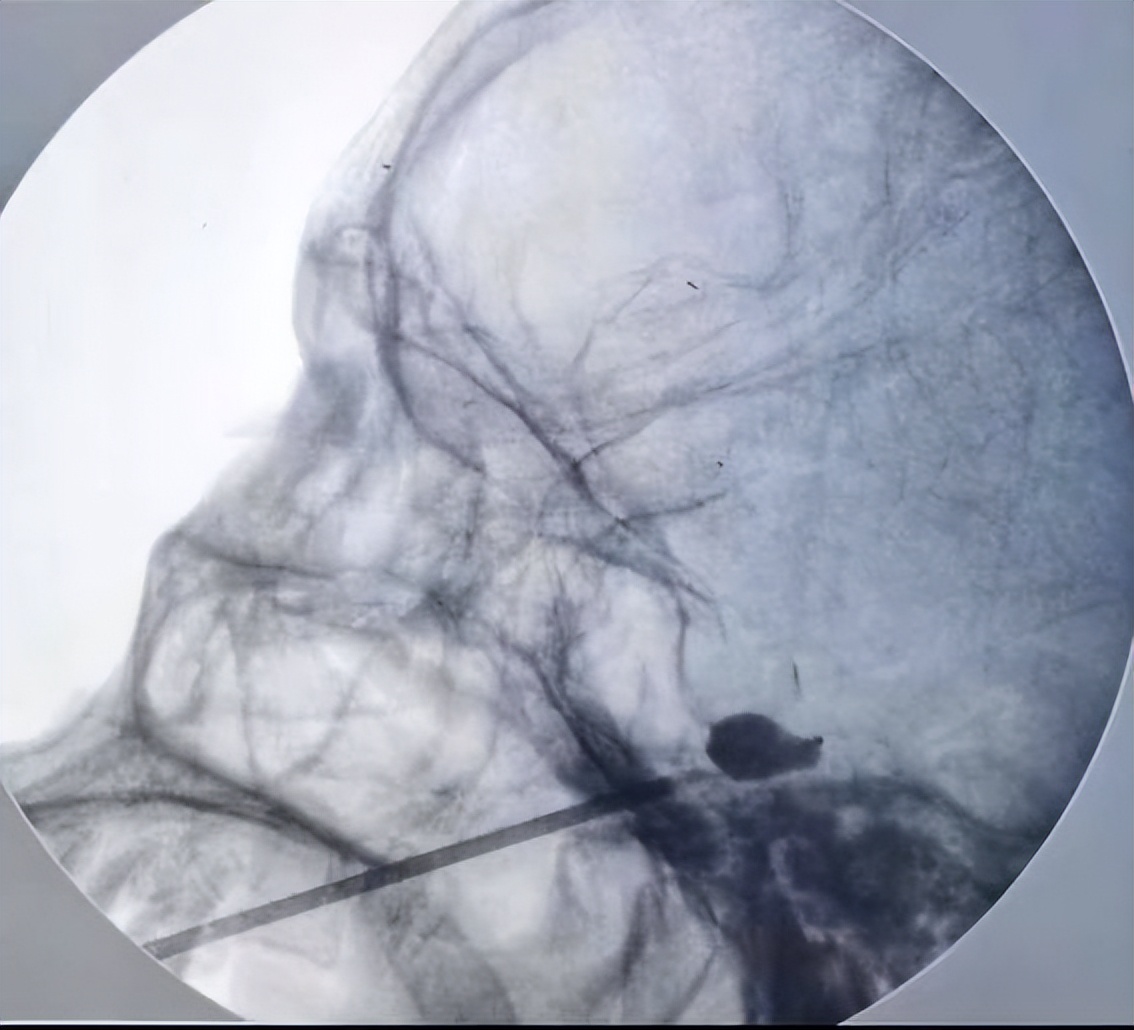

对于三叉神经痛的患者,除了口服药之外,还有更新的微创技术:将一根针穿刺到三叉神经半月节,进行射频热凝或球囊压迫,起到调控神经、治疗疼痛的作用。

射频热凝术,微球囊压迫术